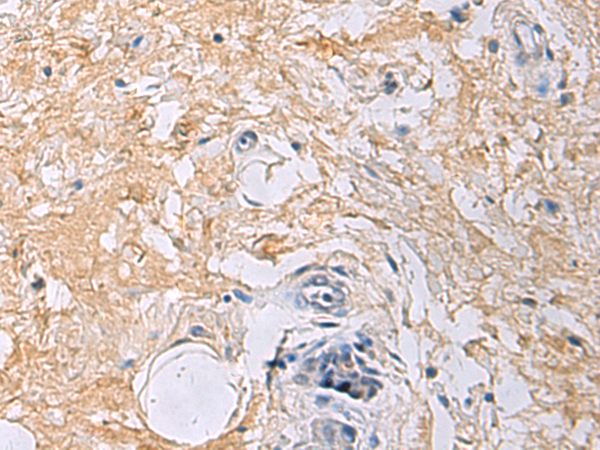

分类: 科研抗体货号: P06620别名: FFA2R; GPR43应用: IHC反应种属: Human

分类: 科研抗体货号: P06654别名: EAA3; EEA3; GLR5; GLUR5; GluK1; gluR-5应用: IHC反应种属: Human